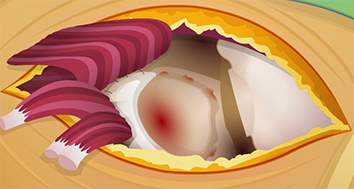

Patient will make a violent kicking motion if it is cut.

Patient won’t be able to feel anything or use her leg again if this is severely damaged or cut.

It will bleed a lot, causing blood pressure to drop.

The gluteus maximus muscle will be less flexible without the sciatic nerve.